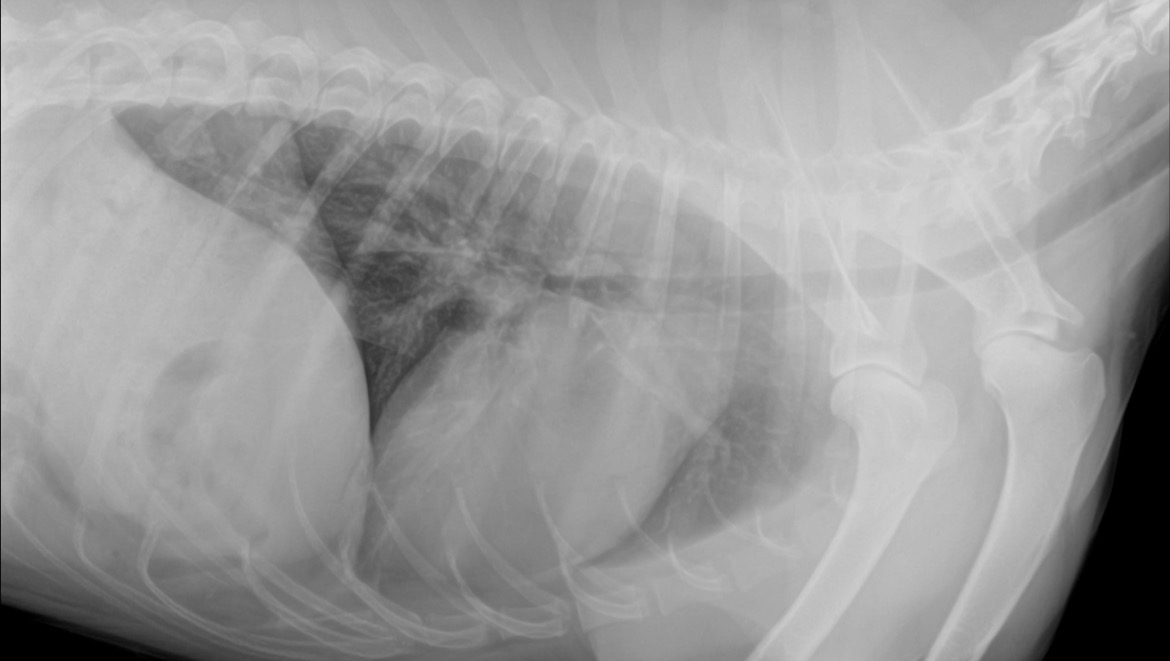

Hello my name is Carissa Tank and I own Scar a 3 year old Australian shepherd. scar is my service dog and has been undergoing a mysterious cough for around 4-5 weeks now. He first started showing symptoms on October 23rd we let it go for a bit. He progressively got worse so we took him to the walk in vet, they told us it was kennel cough and sent us with meds. ($174 for this visit) a week later he was showing no signs of getting better, so he went to urgent care. They ran a culture, took X-rays, and blood work. His X-rays showed pneumonia, so they tried two other meds that ended up working for a few days then he got worse again. ($1021 for this visit) fast forward after he used up those meds no improvement. Called and they gave him two more meds to try ($140 for these meds) no improvement. Suddenly on 11/20 he was at home and started breathing heavily and struggling so now we are at the ER vet awaiting treatment.

his X-rays